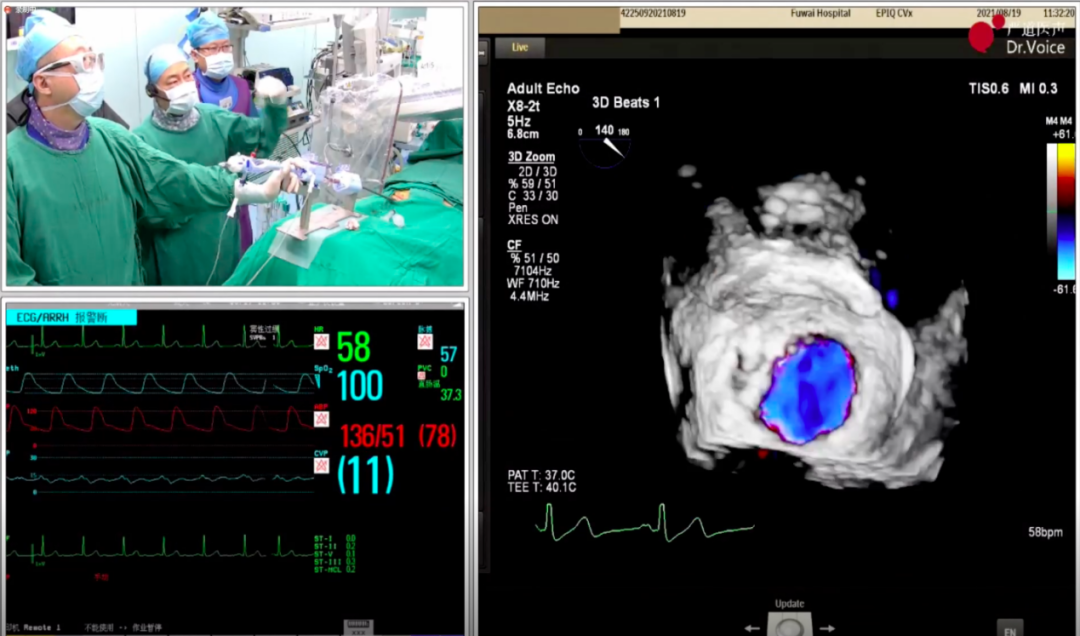

1、手术团队使用MitraClip®独特的三层双调弯导管,经股静脉穿刺,在食道超声引导下完成房间隔穿刺。穿刺后将导管送入左心房,靠近二尖瓣目标位置。术中TEE三维超声可明确显示瓣膜脱垂区域,脱垂区域主要位于二尖瓣前叶A1区及前交界,且面积较大,显著增加手术难度。

三维超声显示瓣膜脱垂区域

初次夹闭时二尖瓣前瓣夹闭部分偏少,调整位置后尝试夹闭,超声显示瓣夹一侧出现少量反流;松开瓣夹后再次调整位置,准确捕获并充分夹闭二尖瓣瓣叶,完成经导管缘对缘修复。

最终夹闭后的超声图像

二尖瓣夹释放后,超声显示反流几近消失,二尖瓣前向峰值流速1.2m/s,平均跨瓣压差3mmHg。患者各项生理指标正常,手术顺利完成,手术操作耗时约120 min。

术后生命体征及超声效果